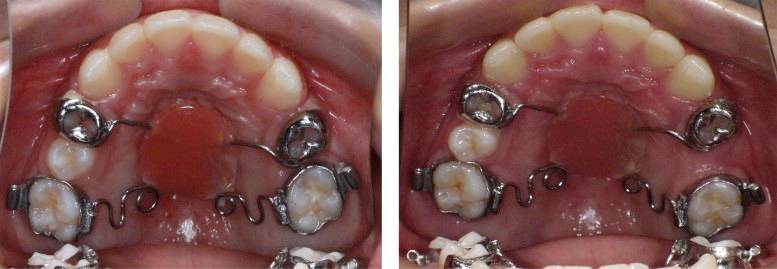

正 畸-正颌联合治疗矫治不对称牙颌面畸形

对于错牙合畸形的治疗,最常见的方式是正畸治疗。而对于一些严重的骨性畸形例如反牙合(地包天)、不对称牙颌面畸形等,则需进行正畸与正颌手术的联合治疗。